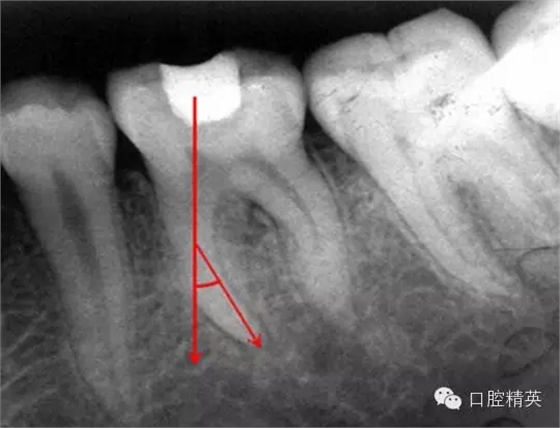

在根管治療的幾年經(jīng)驗中,有些感悟愿與朋友們分享,不到的地方請同仁指正。在做好根管治療時我們首先要攝片分析根管難度選擇合適器具合適方法進(jìn)行治療,根管難度評估:簡單根管(5-10度)

,中等難度根管,(10-25度)復(fù)雜難度根管(大于25度)